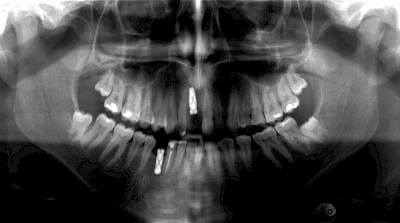

Implantatplanung

Damit Implantate an der richtigen Stelle im Kieferknochen platziert werden könen, gibt es heute vielfältige Möglichkeiten der Planung. In vielen Situationen kann die Erfahrung des Zahnarztes ausreichend sein.

Nicht selten ist jedoch auch eine technisch aufwändigere Vermessung im Vorfeld sinnvoll, z. B.:

- Wenn sich der Kieferknochen abgebaut hat

- Wenn der Nervverlauf im Unterkiefer beachtet werden muss

- Wenn die Ausdehung der Kieferhöhle im Oberkiefer beachtet werden muss

- Wenn wenige Restzähne keine gute Orientierung erlauben

In diesen Fällen kann die Planung mittels verschieden aufwendiger Röntgen-Techniken (Übersichtsaufnahme, DVT) ggf. unter Zuhilfenahme speziell angefertigter Planungsschablonen sinnvoll sein.